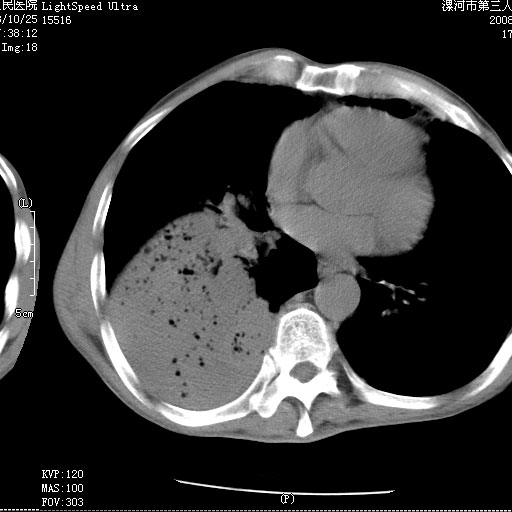

m 老年 发烧、呼吸困难,慢支、肺气肿多年;记的那次是下午大概17:38做的,晚上窒息死亡。

上面的层面就慢性支气管炎肺气肿、肺大泡,别的没有什么、也就不传了。

当时我怀疑:1、阻塞性肺不张早期 2、肺脓肿早期,望老师们发表意见

应该是脓胸的表现,右下肺气管阻塞考虑为痰栓.

你怀疑的有道理,慢支、肺气肿、肺打泡是有了,右下肺的病变有待商议;

首先考虑右下肺炎症并不张,不除外早期肺泡癌改变

病灶边缘清---多个含气小腔---近端未见通畅气管影-----支持-----慢性肺脓肿继发阻塞性肺不张

阻塞性肺不张原因-----脓液未排出

3、细支气管肺泡癌可以排除,病变以斜裂为界,呈大片状高密度影,内可见多发小气泡,表明有产气杆菌感染所致,内无明显的支气管“枯树枝征”表现,再结合其临床改变(细支气管肺泡癌临表表现重、影像表现轻)所以不符合细支气管肺泡癌(炎症型)的改变。

病变按肺叶分布,病变内可见多个小空腔影,未见充气支气管影,中间段支气管管腔肺窗示密度欠均匀,下肺支气管分叉处基底段支气管隐约可见,未见明显狭窄,中叶支气管通畅,

考虑:阻塞性肺炎伴小脓肿形成可能性大。(痰栓可能性大)

右下肺实变,内有弥漫分面小气泡而无支气管征,叶间裂前移,呈臌大之形,而无收缩之状,兼纵隔稍左行移,故。不支持不张,倒支持大叶肺叶,如楼上所说,小气泡不象残留之肺,不可以考虑产气菌感染吗。

阻塞性肺炎,肺脓肿形成。依据,右下支气管不通,大片实变形内可见小气泡。不支持肺不张。